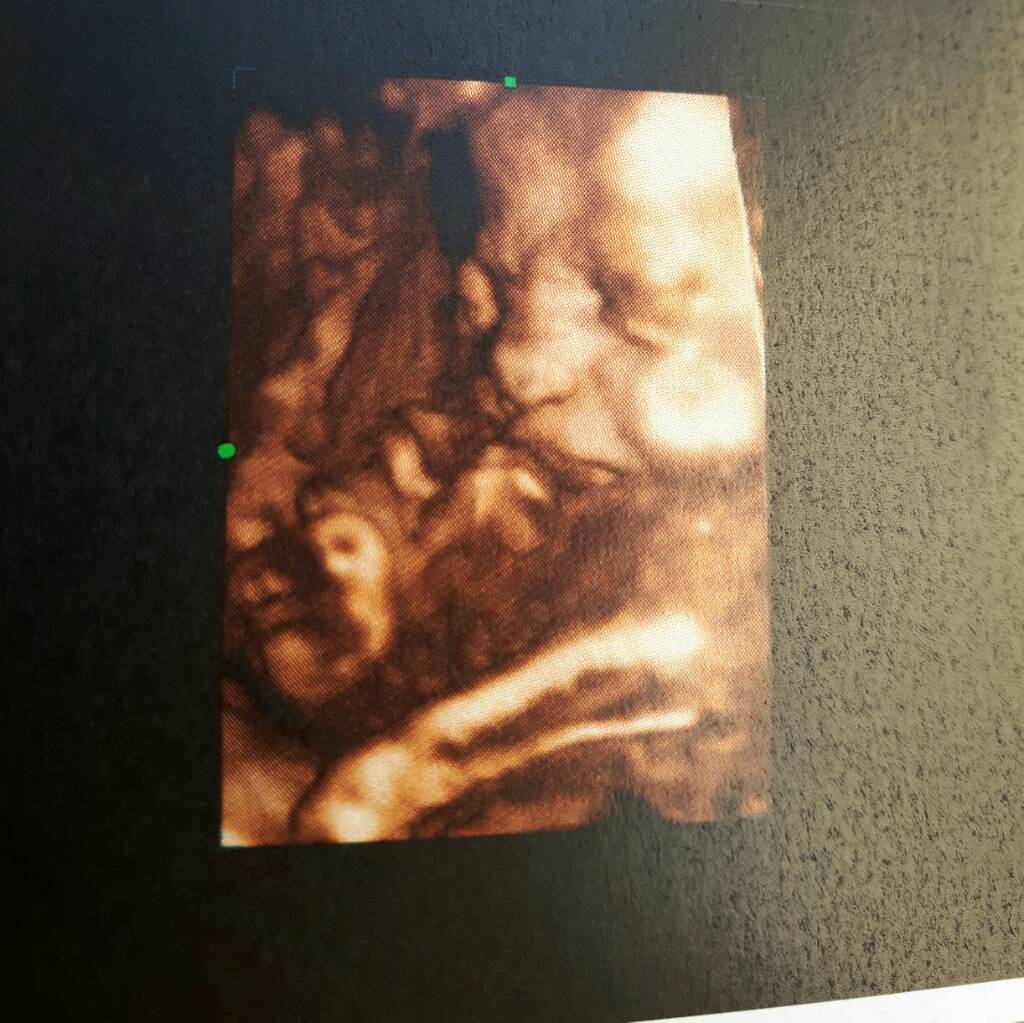

Laski jestem po usg . Masakra !!!!

Wszystko z malym super. W sumie to nie z takim malym . Dzis jest 35.4tydz a moj mezczyzna wazy 3kg. Az drugi raz.mierzylismy i wyszlo 2900g.

Pierwszy synek w tym samym czasie wazyl 2600. Urodzil sie 3600. Lekarz mowil ze jak donosze to bobas do 4kg [emoji33][emoji33][emoji33]